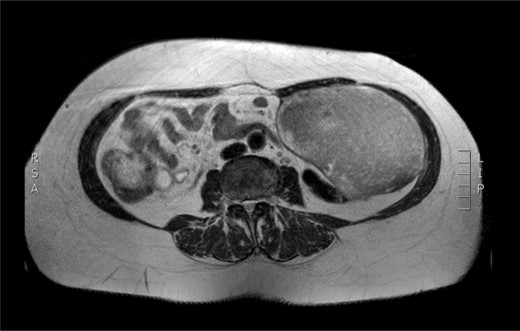

Physical examination revealed a painless, mobile parietal mass on the left anterior abdominal wall, more prominent during cough, of ~13 cm in diameter, with smooth contour and without skin involvement. Laboratory examination including cancer marks showed results within normal limits; hydatid serology (IgG antibodies) was also negative. As ultrasonography results were inconclusive, further imaging with magnetic resonance imaging (MRI) revealed a sizable cystic mass measuring 10 × 13.4 × 11.7 cm, located in the left anterior abdominal quadrant, in the paraumbilical region, between the left internal oblique and the transversus oblique muscle, with projection to the inferior surface of the rectus abdominis. The mass was characterized as a thin-walled cystic lesion, with delayed uptake of intravenous contrast of the wall. High signal intensity was observed on T1-weighted images and low signal intensity on T2-weighted images, with high probability of neoplasia or bleeding (Figs 1–3). No other abdominal or pulmonary lesions were present.

Preoperative MRI. T2 weighted image. Low sign density of the lesion.